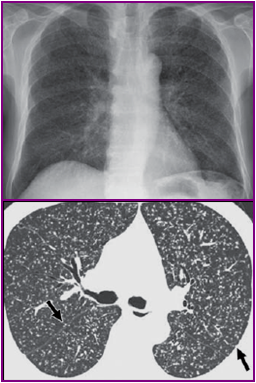

诊断——影像学

X线检查:病灶范围、性质、类型、活动或进展情况,有利于与非结核疾患鉴别及疗效观察。

CT:隐蔽病灶、早期粟粒性肺结核、≥4mm的肺门纵隔淋巴结、淋巴结钙化。

影像学检查

X线检查:85%有肺结核表现,其中90%为活动性病变,粟粒型肺结核占48%。

CT扫描:脑梗塞、脑积水、结核瘤、钙化灶等